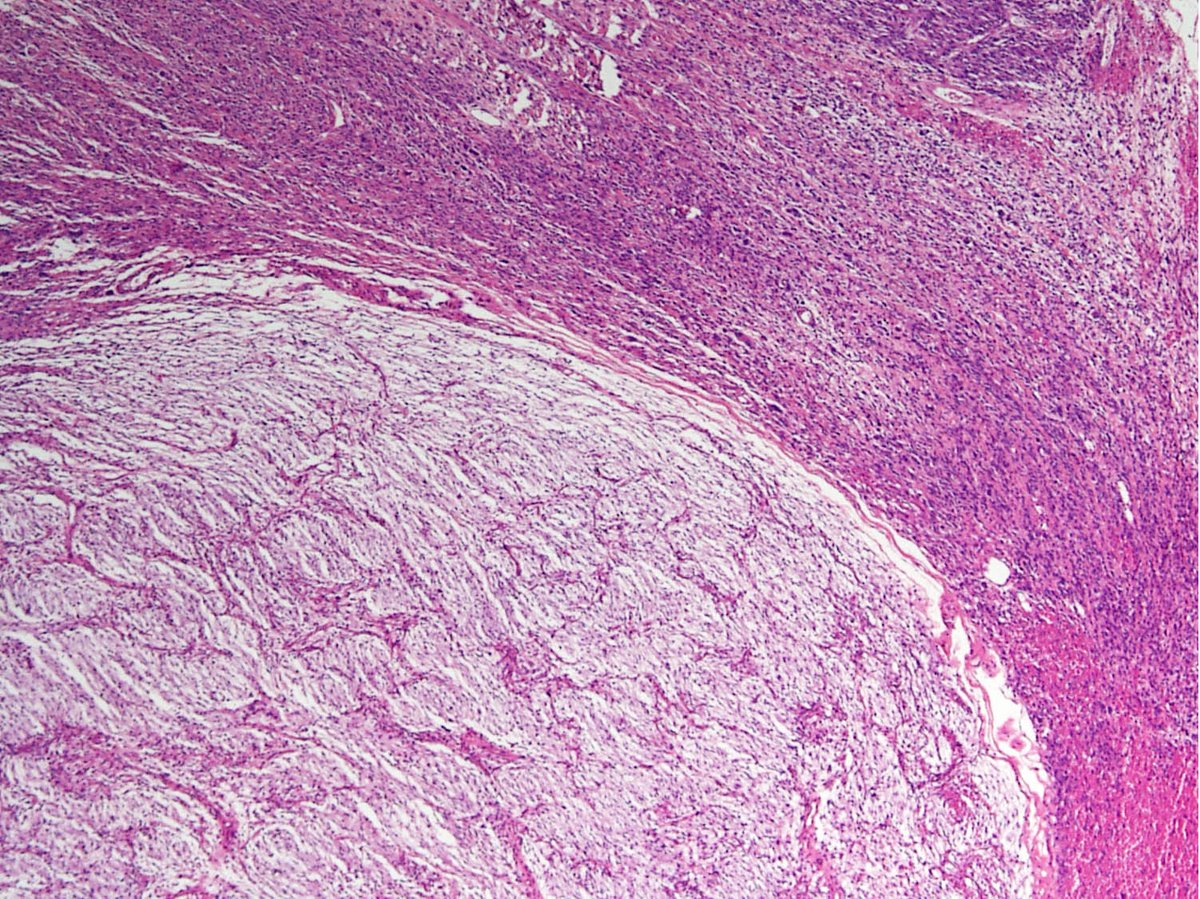

@MirunaPopescu13

❓ Let’s do a quick #BSTPath quiz ❓ 60 y/o F with a retroperitoneal mass 🔪 Follow the 🧵 👇🏽 for the answers & for a short tweetorial (1/11) #PathTwitter #pathoutpic #pathtweetorial